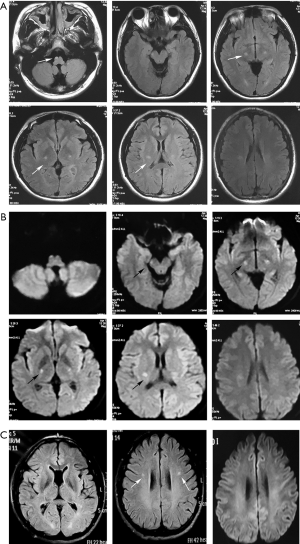

Brain MRI disclosed hyperintensity along the bilateral pyramidal tracts from the centrum semiovale to the cervical segment of the spinal cord on T2-weighted images (T2WI) and fluid-attenuated inversion recovery (FLAIR) images. No gadolinium enhancement was observed in the lesions. The pyramidal tract showed restricted water diffusion on diffusion-weighted imaging (DWI) (Figure 1).

The parents, two paternal uncles, one aunt and grandparents of the proband were all in good health. None of the relatives had focal signs in neurological examination. The father’s GALC activity of leukocytes was 3.5 nmol/g/min (normal range >17.2 nmol/g/min), and brain MRI revealed hyperintensities of the bilateral pyramidal tracts at the centrum semiovale level. Visual radiations were also involved (Figure 1). Thus, the patient, despite having GALC deficiency and characteristic MRI lesions, was asymptomatic. The other family members refused to have further examinations except for genetic testing.

Although the clinical manifestation of adult-onset KD is heterogeneous, involvement of the pyramidal tract is characteristic with an incidence as high as 82–94% (3,11,12). The MRI findings in the present case are consistent with previous reports. In addition, the clinical course of adult-onset KD is considered to be mostly chronic and slowly progressive. Acute progression is very rare. There have been only three reported cases of acute exacerbation similar to the present one (13-15). Meanwhile, only one report (15) mentioned a case of KD with restricted diffusion on DWI corresponding to exacerbation of the condition. In our case, restricted diffusion on DWI consistent with acute progression was also found in the proband but not in the asymptomatic father. Therefore, it seems that DWI is helpful in the follow-up of KD to assess disease progression.

In addition, whether MRI abnormalities occurred before symptoms is a debated issue (12). In our study, scans were analyzed not only for the symptomatic proband but also for the asymptomatic father, which indicates that MRI abnormalities may present before symptom onset. If MRI abnormalities precede symptom onset, the ability of MRI to predict phenotypes in newborn screening populations would be greatly enhanced, and effective therapeutic intervention in asymptomatic patients with late-onset phenotypes may be possible at an early stage of the disease.